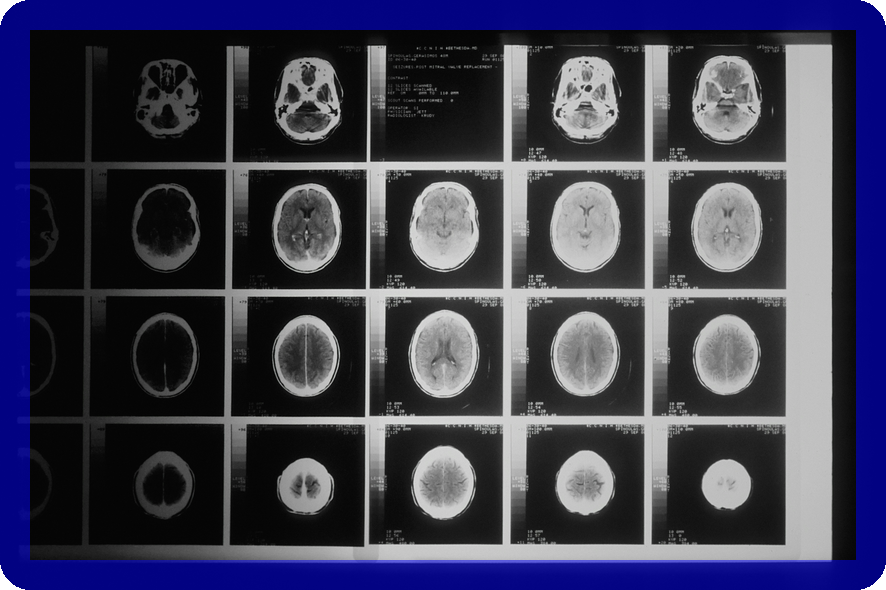

척수종양은 신경계에 큰 영향을 미치는 질병입니다. 이 질환에 대한 이해는 조기 진단과 효과적인 치료를 위해 필수적입니다.

척수종양은 척수 내부 또는 주변에 생기는 종양을 의미하며, 신경계에 심각한 영향을 미칠 수 있습니다. 이 글에서는 척수종양의 주요 종류인 원발성 종양, 내재성 종양, 전이성 종양에 대해 자세히 살펴보겠습니다. 이를 통해 척수종양에 대한 전반적인 이해를 높일 수 있습니다.

척수종양의 치료는 종양의 종류와 위치에 따라 달라지며, 적절한 진단과 치료가 필수적입니다. 본 섹션에서는 효과적인 치료 방법에 대해 자세히 알아보겠습니다.